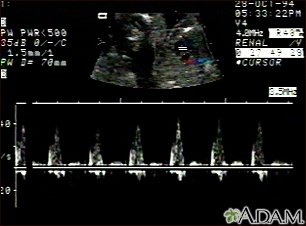

Ultrasound, ventricular septal defect - heartbeatBackUltrasound, ventricular septal defect - heartbeatThis is an ultrasound showing a ventricular septal defect pattern of the fetal heartbeat. Some ultrasound machines have the ability to focus on different areas of the heart and evaluate the heartbeat. This is useful in the early diagnosis of congenital heart abnormalities. E-mail FormEmail ResultsName:Email address:Recipients Name:Recipients address:Message: